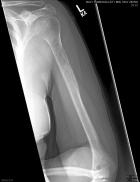

61 year old female with right arm, left hip pain; elevated serum calcium

Zoom image: Radiological image Radiological image.

Zoom image: Cell stain Cell stain.